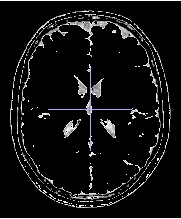

outside select all voxels with a grey level outside threshold1 and threshold2

Threshold1 = 391

Threshold2 = 1078